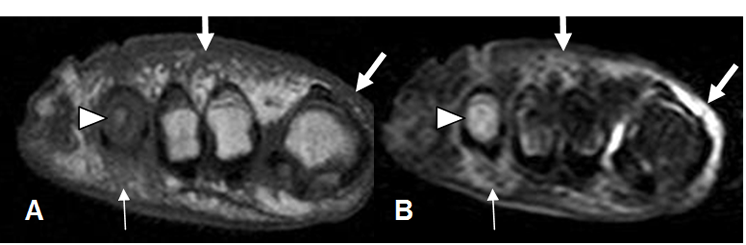

Fig 126 B. Pie diabético. Osteomielitis.

A: RM coronal en T1 y B: RM coronal en STIR. Osteomielitis del 4º metatarsiano hipointenso en T1 e hiperintenso en STIR (Punta de flecha), con cambios inflamatorios en los tejidos blandos. (Flechas delgadas). También hay cambios inflamatorios en el dorso del pie y sobre el 1º dedo. (Flechas gruesas).